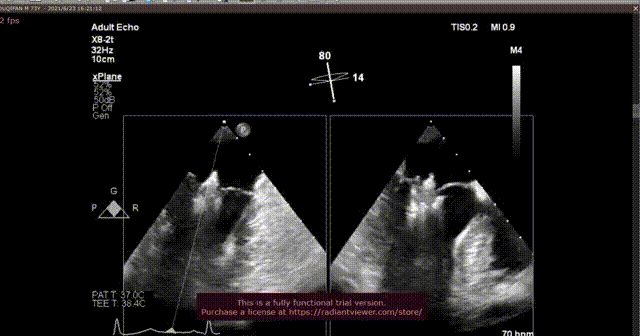

术后即刻超声

术后2D超声

本次手术由心外科尚小珂教授、陈澍教授,心内科钟禹成教授,超声科谢明星教授李贺教授共同完成,法国波尔多里尔大学Thomas Modine教授远程指导。术后即刻超声心动图评估返流降至轻度,夹合器锚定良好、器械顺利撤出体外,手术取得圆满成功。术后第二天超声心动图评估返流为轻度,夹合器稳定。术后尚小珂教授表示:“经皮二尖瓣夹合器的应用成功,给大量无法耐受传统开胸手术的患者提供新的希望,微创介入术式必定会被越来越多的患者接受。本器械最大的优势在于其结构设计简单易上手,学习曲线短且效果显著,不仅针对退行性二尖瓣病变,对于心衰功能性二尖瓣反流一样可达到治疗效果。迄今为止,武汉协和医院仍然是华中唯一可以同时开展四个瓣膜介入手术的中心。